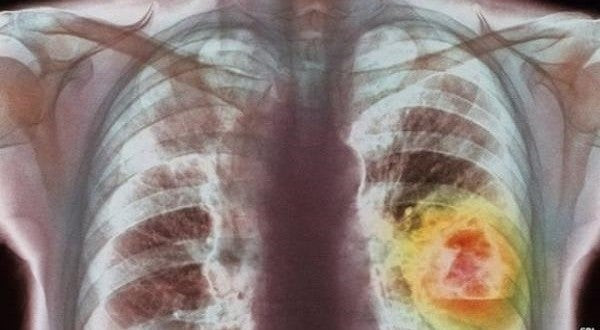

Η φυτική ουσία που μπορεί να καταστρέψει το 90% των κυττάρων του καρκίνου του πνεύμονα!

Δείτε την φυτική ουσία που μπορεί να καταστρέψει το 90% των κυττάρων του καρκίνου του πνεύμονα! Ο καρκίνος του πνεύμονα είναι μια ασθένεια που χαρακτηρίζεται από ανεξέλεγκτη ανάπτυξη τ...